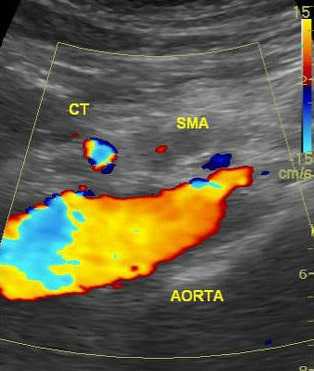

Во время допплерографии ветви аорты и она сама окрашиваются в разные цвета, что помогает специалисту УЗИ сделать заключение о состоянии кровотока.

Возможности ультразвуковых приборов позволяют не только оценить размеры, форму и структуру стенки сосуда, но и исследовать характеристики кровотока. Это достигается с помощью доплерографии и цветного допплеровского картирования. Доплерография основана на регистрации ультразвукового сигнала от движущихся эритроцитов и изменении скорости этого сигнала в зависимости от приближения или удаления этих частиц к датчику. Скорость кровотока, определяемого доплерографией, является показателем проходимости сосудов ниже места исследования или в местах сужения сосуда. В суженых местах она значительно усилена; если же существует препятствие для оттока крови ниже места исследования, то скорость снижается.

Во время УЗИ аорты и брюшных сосудов врач изучает размер аорты и её просвет, насколько равномерно она окрашивается при доплеровском картировании. Расширение брюшной аорты более 4 см говорит в пользу аневризмы. Ультразвуковая диагностика позволяет оценить состояние артерий почек, кишечника, печени и желудка. Можно выявить расширение артерий внутренних органов. При осложнённых аневризмах возможно выявление забрюшинной гематомы при разрыве, жидкости в брюшной полости, тромбоза аорты или висцеральных артерий. Часто на хорошем УЗИ-сканере удаётся выявить расслоение стенки сосуда, её надрывы и атеросклеротические бляшки. УЗИ брюшного отдела аорты и висцеральных ветвей длится около 25-40 минут. После обследования можно сразу возвращаться к обычным занятиям.